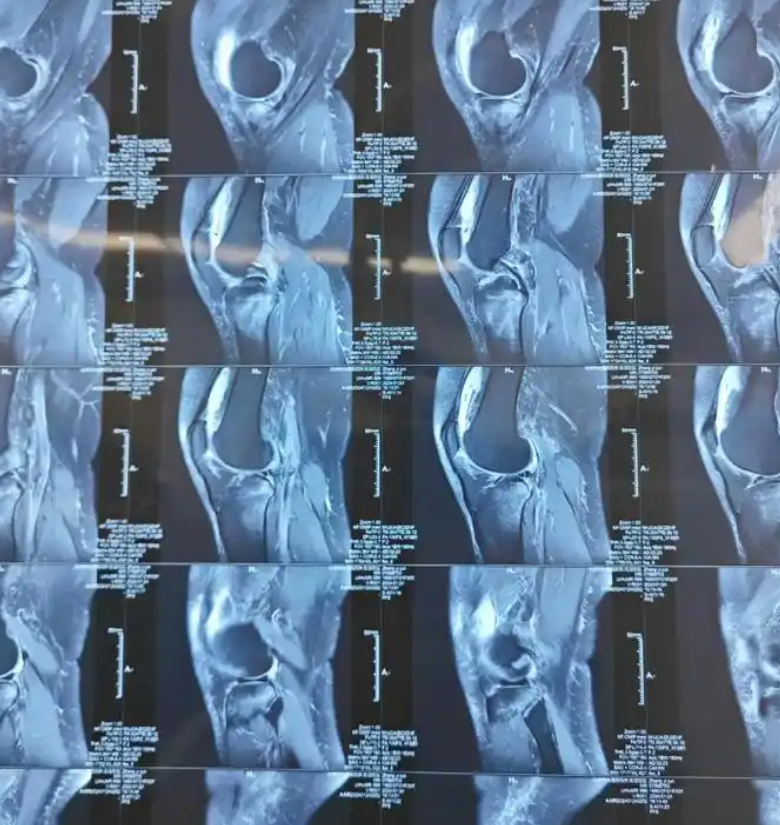

何时需要就医若骨头老响伴有疼痛肿胀僵硬活动受限等症状,或响声频繁持续时间较长,应及时就医医生会通过身体检查和影像学检查如X光MRI明确原因,并制定治疗方案日常缓解方法保持适当运动,增强肌肉力量,改善关节灵活性注意姿势,保持正确坐姿和站姿,避免长时间固定姿势控制体重,减轻。